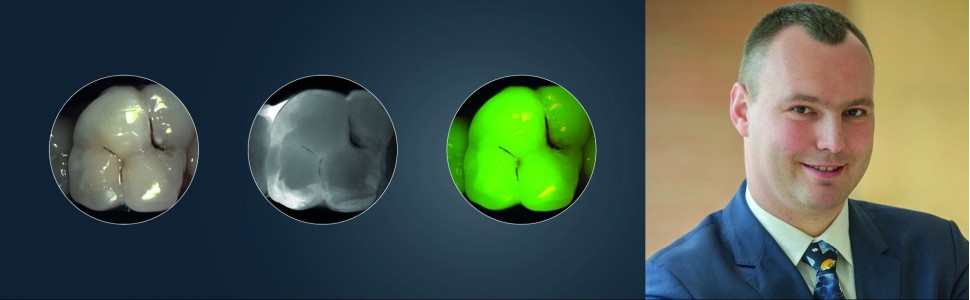

Nowa wersja urządzenia DIAGNOcam Vision Full HD (KaVo) pozwala na jednoczesną rejestrację trzech obrazów tej samej sytuacji klinicznej w ustach pacjenta. Wykonywane są zdjęcia:

- z wykorzystaniem technologii NILT,

- z wykorzystaniem zwykłej kamery wewnątrzustnej,

- z wykorzystaniem kamery fluorescencyjnej.

Takie potrojone obrazowanie pozwala na dokładną diagnostykę zmian próchnicowych, ewentualnej obecności płytki bakteryjnej na powierzchni zębów oraz prezentację wyników diagnostycznych pacjentom w sposób nie budzący żadnych wątpliwości. Cały proces badania realizowany jest tym samym urządzeniem, podłączonym do komputera i monitora. Lekarz dostaje do dyspozycji trzy obrazy: diagnostyczny z kamery IR (najbardziej mu potrzebny), rzeczywisty z kamery wewnątrzustnej (najbardziej trafiający do pacjenta), oraz fluorescencyjny (najbardziej motywujący do leczenia i poprawy higieny), a wszystkie obrazy mają dokładnie tą samą projekcję i łatwo je ze sobą porównać. Technologia NILT umożliwia wykonanie prześwietlenia zęba i zdiagnozowanie zmian próchnicowych o każdym stopniu zaawansowania.

Pierwsze z trzech wykonanych jednocześnie zdjęć stałego zęba trzonowego przy pomocy DIAGNOcam z wykorzystaniem kamery rejestrujące światło widzialne. Ten obraz jest najbardziej czytelny dla pacjenta.

Drugie z trzech wykonanych jednocześnie zdjęć przy pomoc DIAGNOcam z wykorzystaniem technologii NILT i kamery rejestrującej światło podczerwone. Ten obraz jest najbardziej przydatny diagnostycznie dla lekarza stomatologa.

Trzecie z trzech wykonanych jednocześnie zdjęć przy pomoc DIAGNOcam z wykorzystaniem kamery fluorescencyjnej. Ten obraz jest przydatny diagnostycznie dla lekarza stomatologa i może zostać wykorzystany do motywacji pacjenta dla poprawy higieny jamy ustnej.